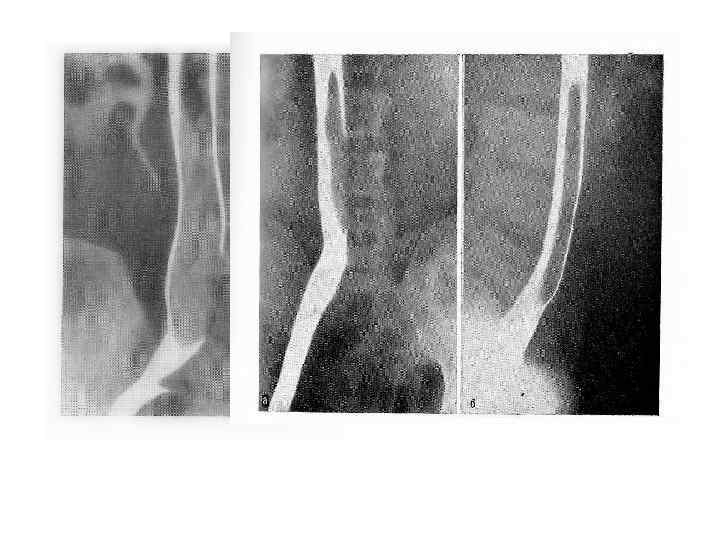

«Флотирующий» тромб в нижней полой вене